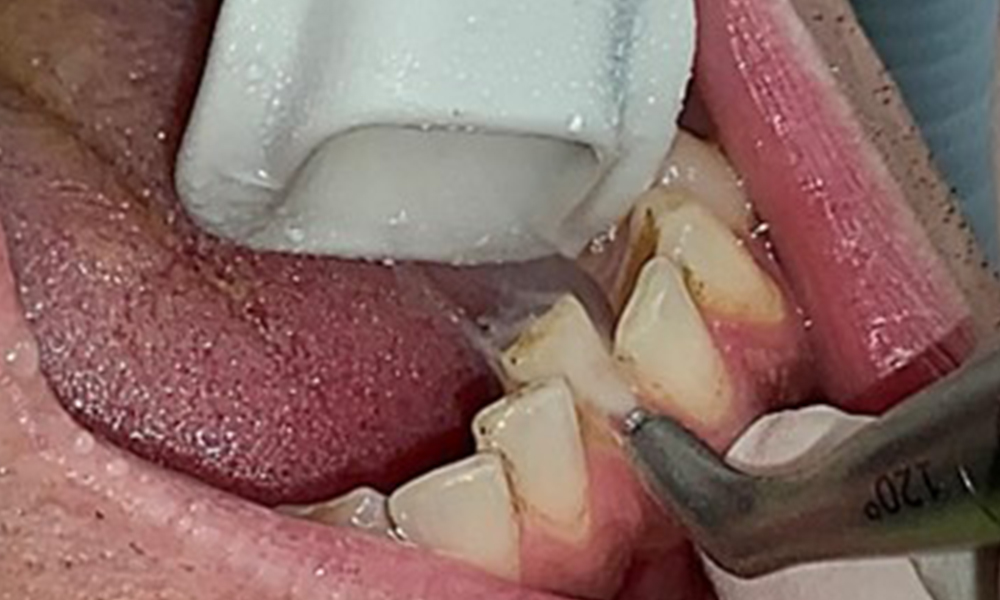

The objective would be to control disease risk by removing supragingival and subgingival biofilm. The instruments can be selected based on patient needs. First, calculus and any concretions must be removed using ultrasonic and/or manual instruments (Fig. 10).